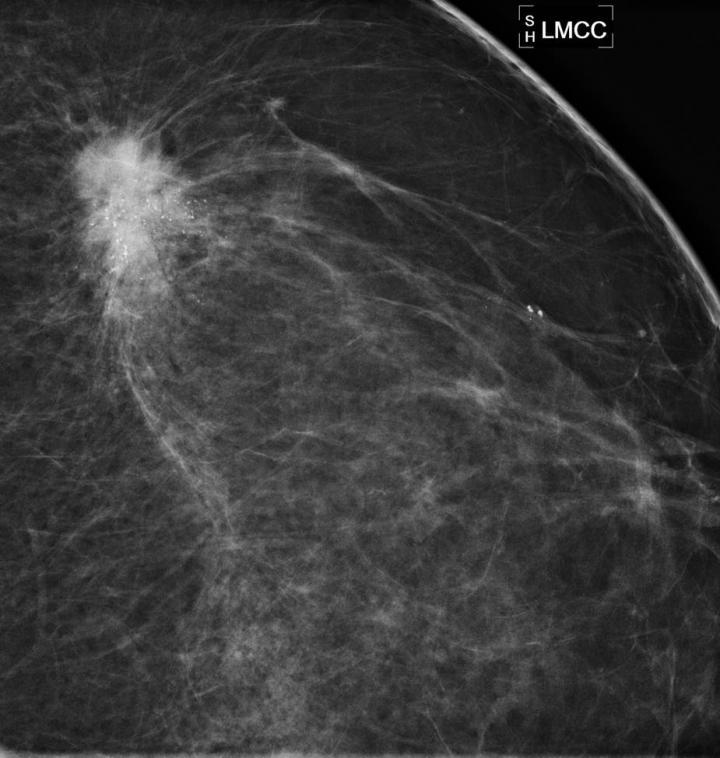

A spot magnification view demonstrates an irregular spiculated mass with associated calcifications in the upper outer left breast.

(Photo Credit: RSNA)